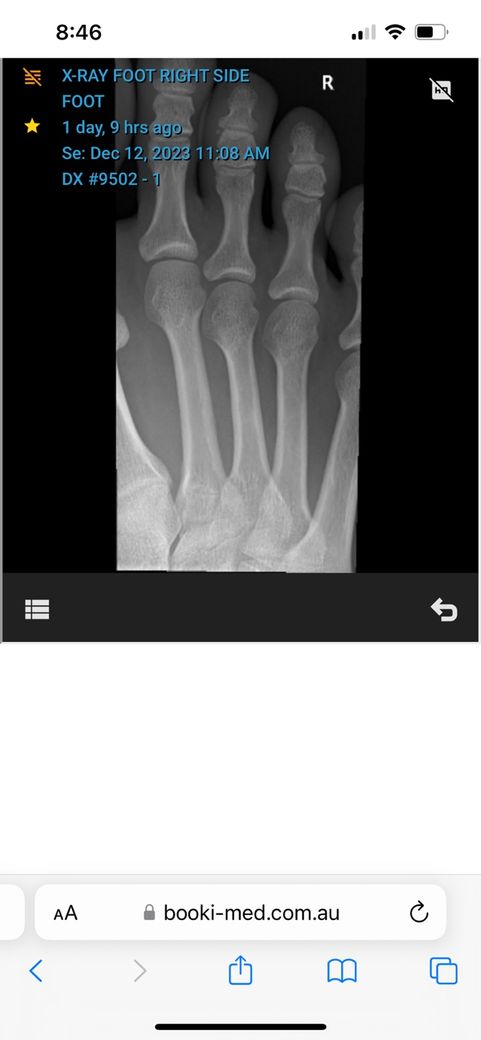

• 2번 째 사진

• 3번 째 사진

• 올리신 엑스레이 사진을 통해서 보았을 때에는 뼈의 골절 등 이상 소견이 보이지 않습니다. 다만 인대나 근육 등 부위에 대해서는 평가가 제한됩니다. 아무래도 추측건대 발레를 시작하고 발 부위에 충격이 반복되다 보니 충격으로 인한 조직 부종 및 염증 등이 생겼을 가능성이 높아 보입니다. 엑스레이 검사를 통해서는 보다 정밀한 소견들을 알 수 없습니다.